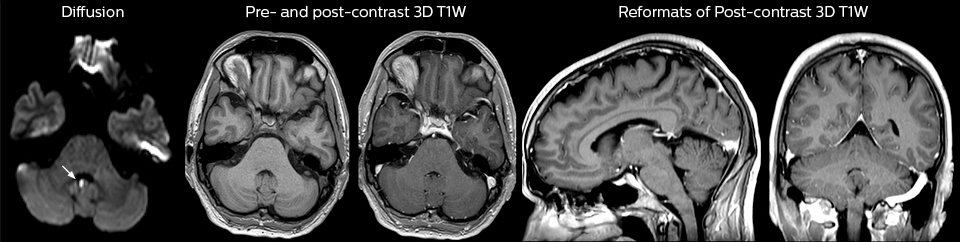

Guidance on appropriate use of MRI

A range of protocol sheets was developed to help ensure that referring physicians order the most appropriate MRI exam. The optimized MRI protocols also include 3D contrast-enhanced imaging, allowing neurosurgeons to comfortably use the isotropic data in the operating room while performing stereotaxic surgery.